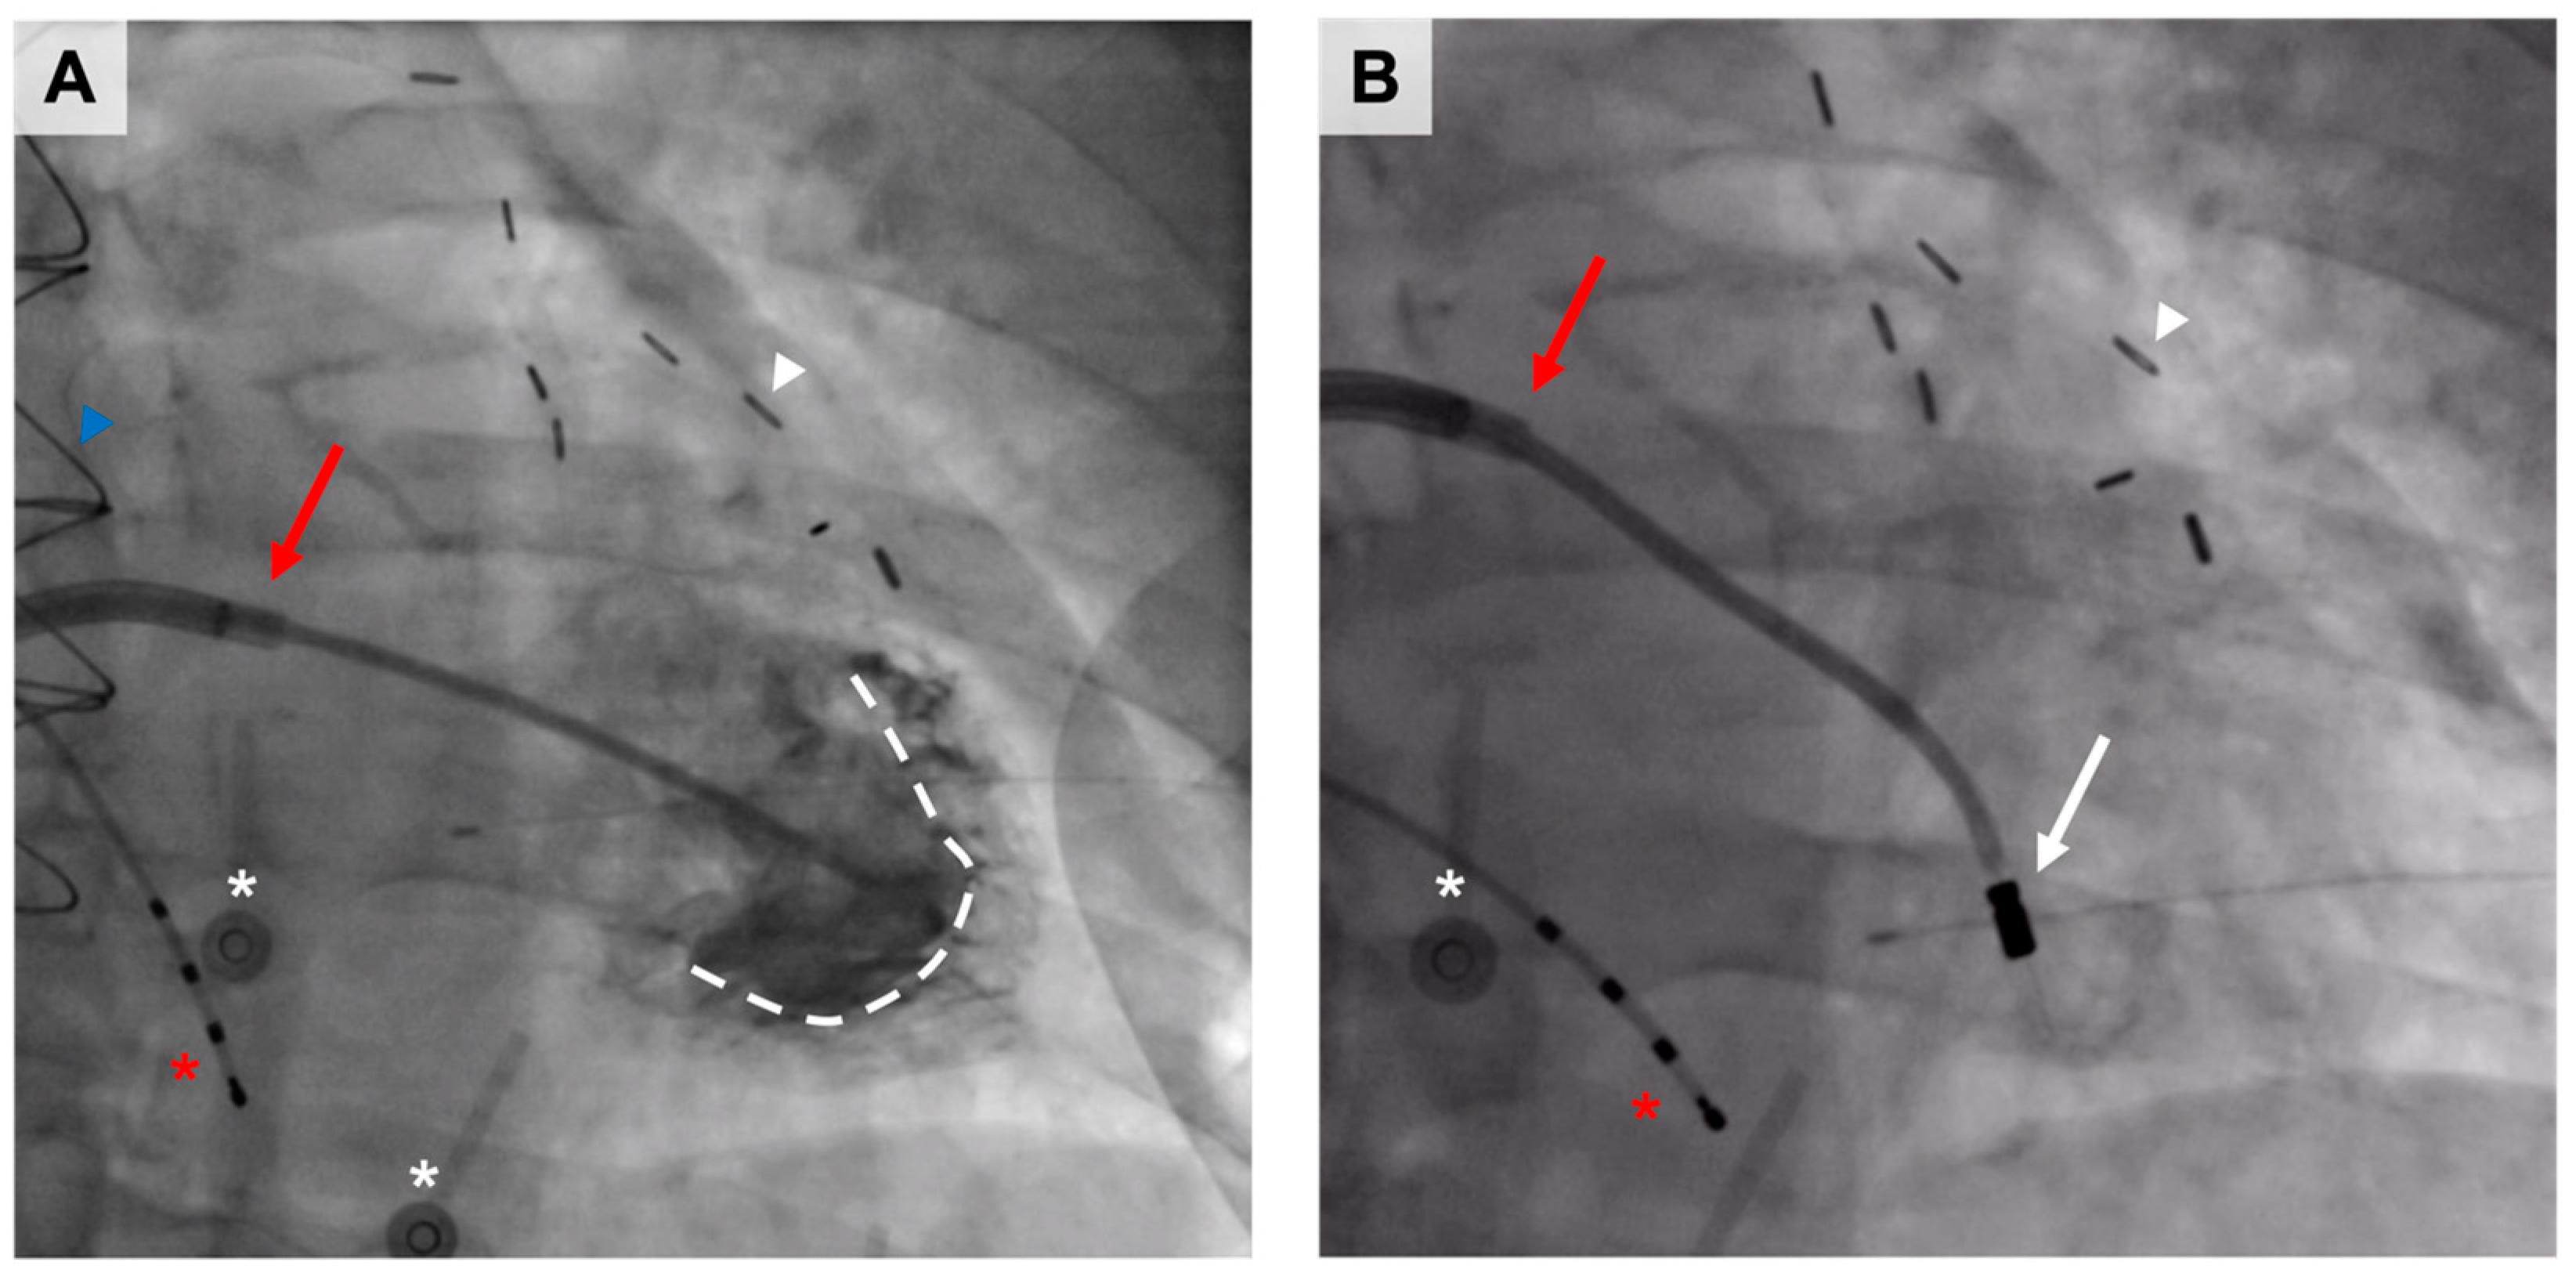

- Hartikainen, J.; Hassinen, I.; Hedman, A.; Kivelä, A.; Saraste, A.; Knuuti, J.; Husso, M.; Mussalo, H.; Hedman, M.; Rissanen, T.T.; et al. Adenoviral intramyocardial VEGF-DΔNΔC gene transfer increases myocardial perfusion reserve in refractory angina patients: A phase I/IIa study with 1-year follow-up. Eur. Heart J. 2017, 38, 2547–2555, Erratum in: Eur. Heart J. 2018, 39, 1652. [Google Scholar] [CrossRef]

- Leikas, A.J.; Laham-Karam, N.; Agtereek, E.; Peltonen, H.M.; Selander, T.; Korpisalo, P.; Holappa, L.; Hartikainen, J.E.K.; Heikura, T.; Ylä-Herttuala, S. Efficacy and Safety of Clinical-Grade Human Vascular Endothelial Growth Factor-DΔNΔC Gene Therapy Containing Residual Replication-Competent Adenoviruses. Hum. Gene Ther. 2021, 32, 761–770. [Google Scholar] [CrossRef] [PubMed]

- Pajula, J.; Lähteenvuo, J.; Lähteenvuo, M.; Honkonen, K.; Halonen, P.; Hätinen, O.P.; Kuivanen, A.; Heikkilä, M.; Nurro, J.; Hartikainen, J.; et al. Adenoviral VEGF-DΔN ΔC gene therapy for myocardial ischemia. Front. Bioeng. Biotechnol. 2022, 10, 999226. [Google Scholar] [CrossRef]

- Leikas, A.J.; Hassinen, I.; Hedman, A.; Kivelä, A.; Ylä-Herttuala, S.; Hartikainen, J.E.K. Long-term safety and efficacy of intramyocardial adenovirus-mediated VEGF-DΔNΔC gene therapy eight-year follow-up of phase I KAT301 study. Gene Ther. 2022, 29, 289–293. [Google Scholar] [CrossRef]

- Leikas, A.J.; Hassinen, I.; Kivelä, A.; Hedman, A.; Mussalo, H.; Ylä-Herttuala, S.; Hartikainen, J.E.K. Intramyocardial adenoviral vascular endothelial growth factor-D∆N∆C gene therapy does not induce ventricular arrhythmias. J. Gene Med. 2022, 24, e3437. [Google Scholar] [CrossRef]

- Hedman, M.; Hartikainen, J.; Syvänne, M.; Stjernvall, J.; Hedman, A.; Kivelä, A.; Vanninen, E.; Mussalo, H.; Kauppila, E.; Simula, S.; et al. Safety and feasibility of catheter-based local intracoronary vascular endothelial growth factor gene transfer in the prevention of postangioplasty and in-stent restenosis and in the treatment of chronic myocardial ischemia: Phase II results of the Kuopio Angiogenesis Trial (KAT). Circulation 2003, 107, 2677–2683. [Google Scholar] [CrossRef] [PubMed]

- Hedman, M.; Muona, K.; Hedman, A.; Kivelä, A.; Syvänne, M.; Eränen, J.; Rantala, A.; Stjernvall, J.; Nieminen, M.S.; Hartikainen, J.; et al. Eight-year safety follow-up of coronary artery disease patients after local intracoronary VEGF gene transfer. Gene Ther. 2009, 16, 629–634. [Google Scholar] [CrossRef] [PubMed]